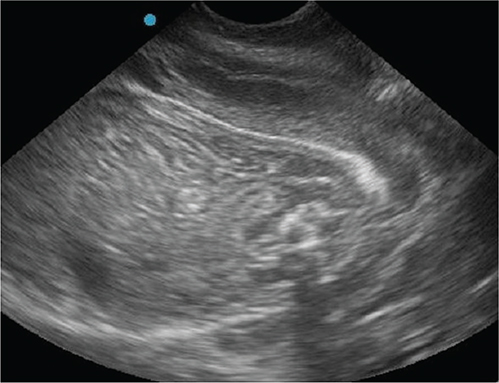

Fig. 3.

Figure 3. Transabdominal ultrasonographic image of fetal demise, note the hyperechoic foci around fetus (air shadowing), and fetus is poorly defined due to autolysis.

The dog was presented for an outpatient reexamination once more (on day 56 after breeding). The dog had 2 episodes of vomiting since prior visit and was trembling in the car for an hour prior to the appointment. The dog had lost 0.5 kg since prior visit, was tachycardic (160/bpm), had mild erythema of the skin and ear pinnae, and was mildly hyperthermic (39.4°C). There was continued vulvar discharge and initial mammary secretions from a few teats, consistent with colostrum. Due to the concern for systemic inflammatory response syndrome (SIRS)6 on clinical examination (elevated temperature and tachycardia), bloodwork was performed. Patient had moderate normocytic normochromic anemia of pregnancy, with a marked neutrophilia and a left shift, and mild monocytosis. A mild hypoglycemia and mild hypocalcemia were also noted (Table). Progesterone concentrations were lower (1.10 ng/ml). Targeted transabdominal ultrasonography revealed similar findings as before (multiple normal viable fetuses and 1 dead fetus [Figure 4]). Further maturation of the live fetuses was evident by slight distinction of the cortical and medullary parenchyma of fetal kidneys (Figure 5) and a more thickening of gastrointestinal tract layers in two of the fetuses7 (Figure 6). Given the patient’s deterioration and concerning laboratory findings, immediate cesarean surgery with ovariohysterectomy was again recommended; however, surgery was declined. Recommendation was made to discontinue terbutaline (Brethine®, Hikma Pharmaceuticals PLC) and altrenogest (Regu-Mate®, Merck Animal Health), to allow the dog to whelp at home. Amoxicillin and clavulanate potassium (Clavamox®, Zoetis) and ciprofloxacin (Cipro®, Bayer HealthCare Pharmaceuticals Inc.) were continued.